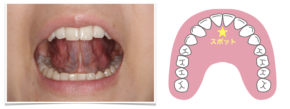

子どもの歯並び予防のMFT⑤〜舌の位置のトレーニング(スポットポジション)〜

2024.06.06

スポットポジション

普段何もしていないリラックスしている時(口を閉じているとき)や、飲み込む時の舌の先の正しい位置を覚えるトレーニングをご紹介します。

舌先が触れる位置を『スポット』と呼び、上の前歯の後ろの付け根から5〜10mmくらい後方くらいのプクっとした膨らみの付け根あたりです。

①スティックでスポットを触り、ゆっくり5秒間

②スティックを離し、同じ場所を舌の先で触り、つけたまま5秒間

姿勢を良くして、鏡を見ながら①と②を交互に5〜10回行います。

このとき、舌の先を丸めないで、舌の脇を締め、先を尖らせてください。

ご家庭でも簡単に行えるトレーニングですので、ぜひお試しください。

分らない方は、保険診療の適応内で指導できますのでお気軽にご相談下さい。